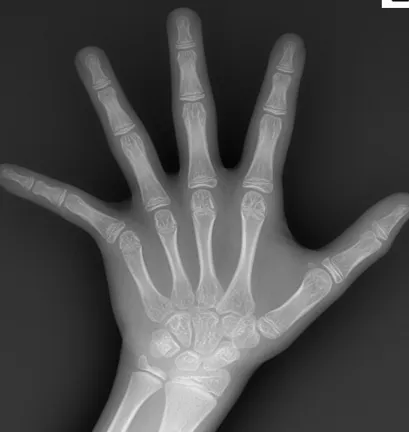

性激素加速骨骼成熟

性早熟儿童体内性激素(如雌激素、雄激素)过早升高,会促使骺板细胞加速增殖、分化并提前骨化。

骺板是长骨两端的软骨组织,负责骨骼生长。

一旦骺板过早闭合,长骨便无法继续生长,即使生长激素正常分泌,也难以实现身高进一步发育,从而限制最终身高。